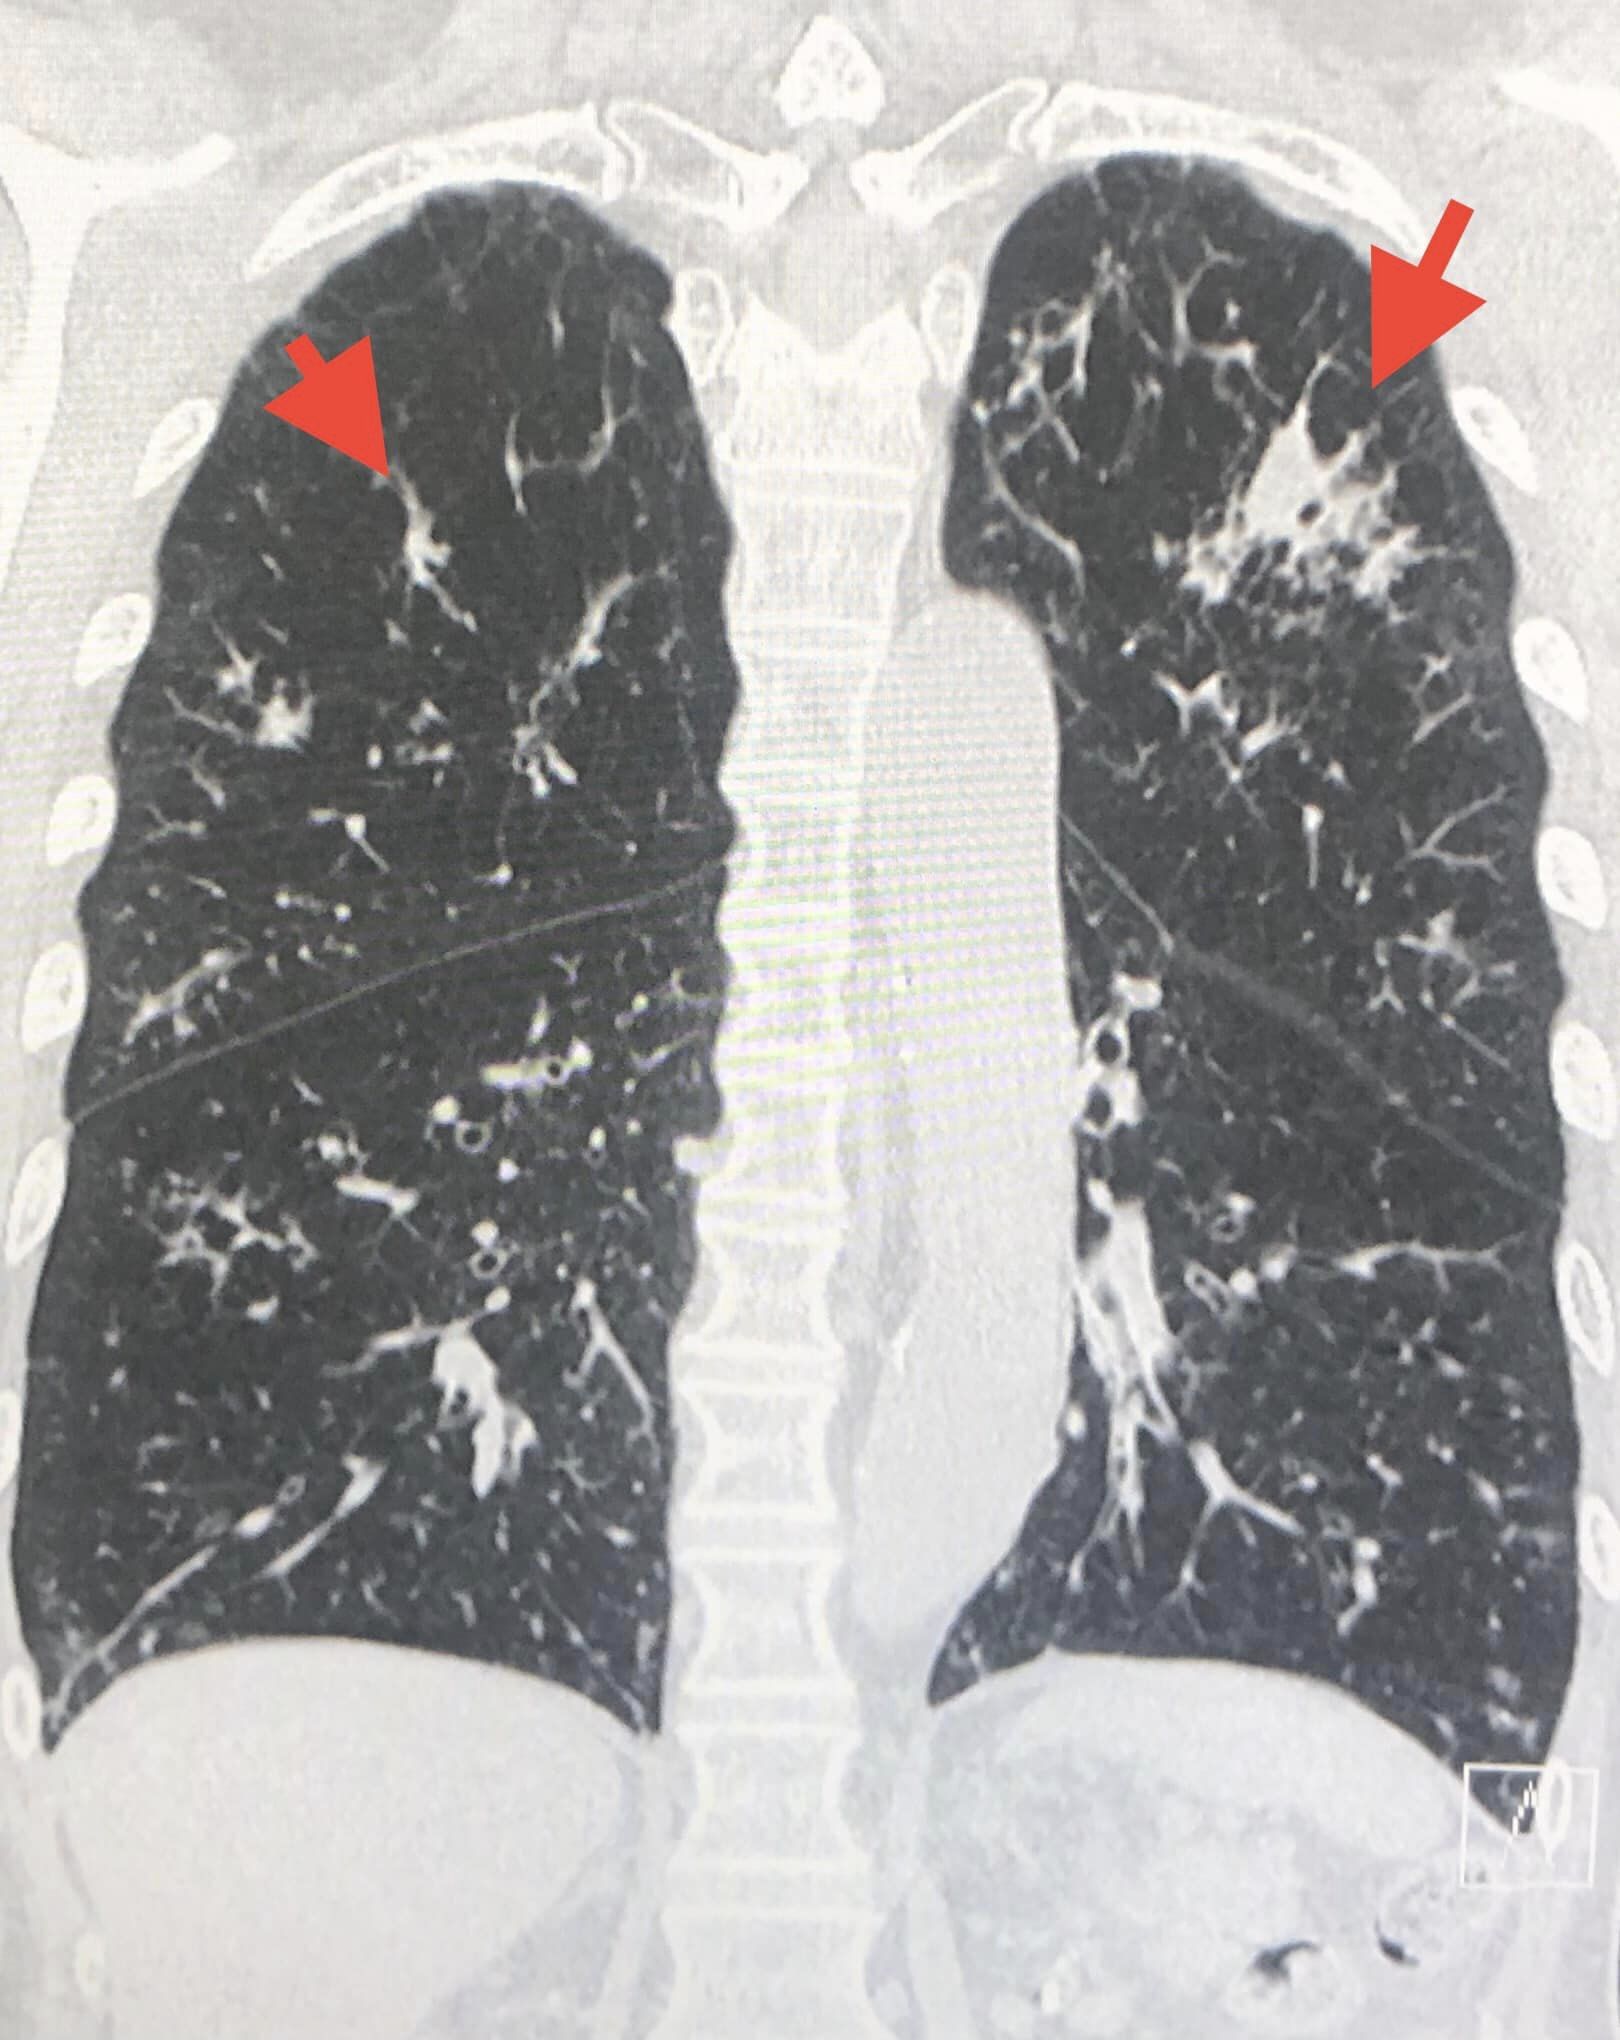

ตรวจร่างกาย ไม่มีไข้ อุณหภูมิ 37 องศาเซลเซียส ฟังปอดมีเสียงวี๊ด เอกซเรย์ปอด มีปื้นขาวเล็กๆในปอด 2 ข้าง (ดูรูป) คอมพิวเตอร์สแกนปอดมีฝ้าหลายจุดกระจายในปอด 2 ข้าง (ดูรูป) ทำหัตถการส่องกล้องเข้าไปในหลอดลม( Bronchoscopy) พบเสมหะเหลืองข้นเหนียวมากในหลอดลมทั้ง 2 ข้าง ดูดออกมาได้เยอะมาก ส่งน้ำล้างปอด ย้อมไม่พบเชื้อวัณโรค ย้อมพบเชื้อราสาย เพาะเชื้อราขึ้นเชื้อรา Aspergillus fumigatus และ Rhizopus spp. (ดูรูป) ส่งน้ำล้างปอด bronchial Aspergillus galactomannan antigen ให้ผลบวก

สรุป: ปอดอักเสบเกิดจากการติดเชื้อรา ได้ให้ยาฆ่าเชื้อราตัวใหม่ Isavuconazole ซึ่งมีราคาแพงมากสามารถครอบคลุมฆ่าเชื้อราได้ทั้ง 2 ชนิด หลังกินยาผู้ป่วยดีขึ้นช้าๆ ไอน้อยลง เหนื่อยน้อยลง

ผู้ป่วยมีภูมิคุ้มกันต่ำจากการกินยาเสตียรอยด์ต่อเนื่องเป็นปี บ้านของผู้ป่วยติดกับโกดังเก็บข้าวโพดเลี้ยงสัตว์ ผู้ป่วยหายใจสปอร์ของเชื้อราที่เจริญงอกในเมล็ดข้าวโพดเข้าไปในปอด ต้องให้ยาฆ่าเชื้อราตัวใหม่ต่อเนื่องนานหลายเดือน จนกว่าเอกซเรย์ปอดกลับมาเป็นปกติ